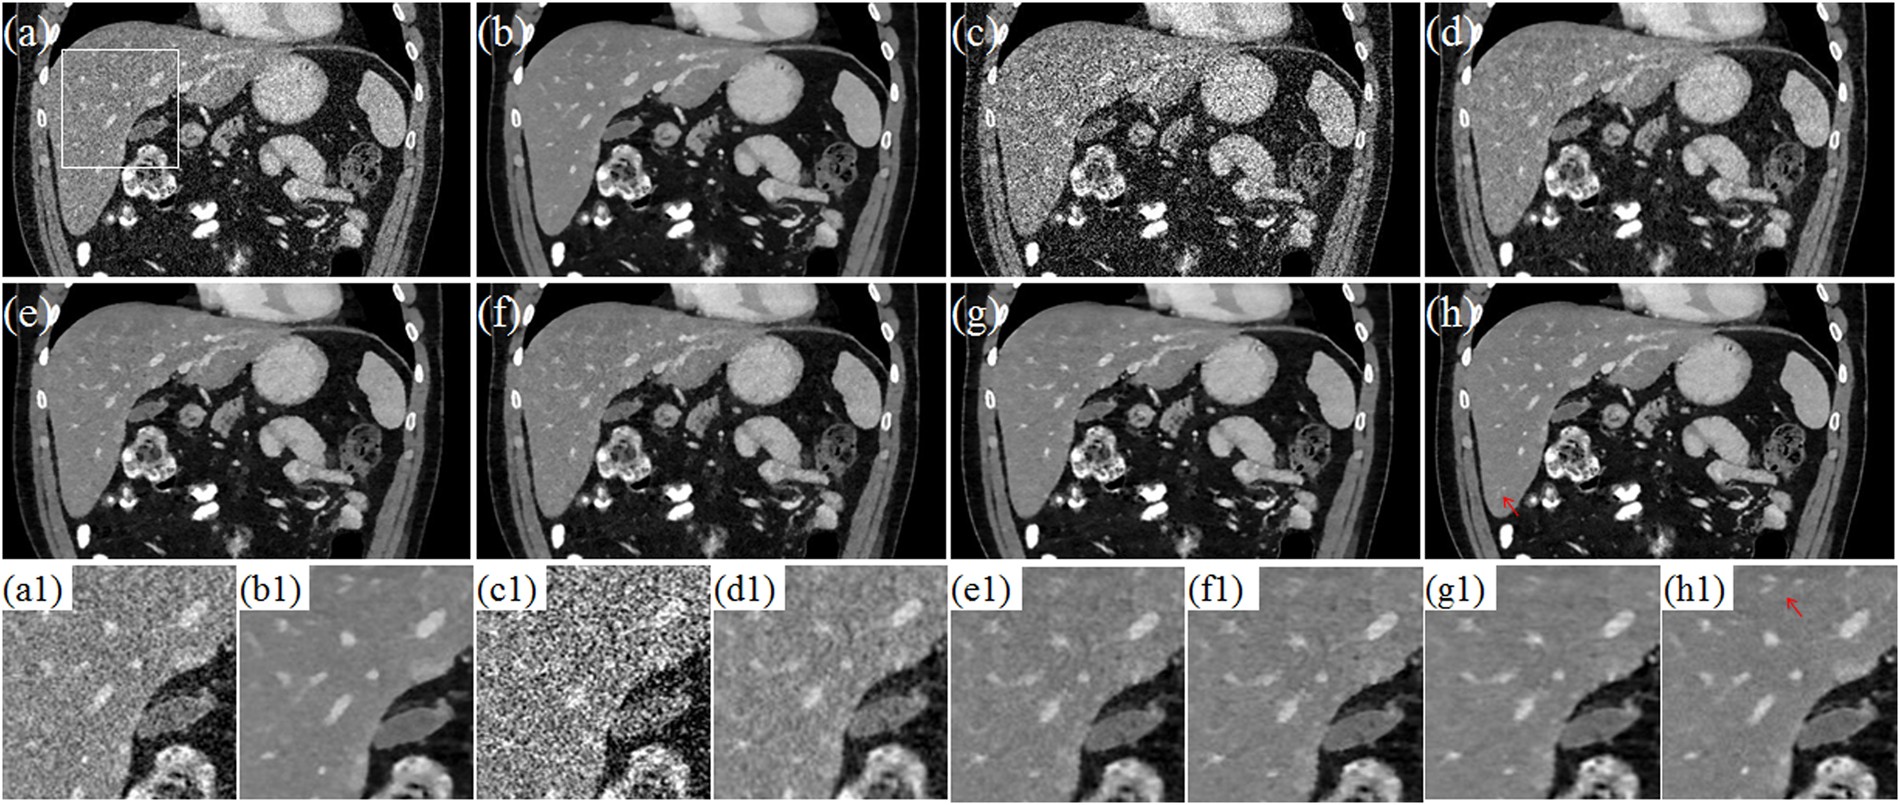

Figure 13

The coronary views for Data C2. (a–b) are the images reconstructed by the FDK and TV methods for standard dose protocol; (c–h) are the images reconstructed by the FDK, DFR-post, TV, PICCSDFR, GDSIR, DP-PICCS methods for low dose protocol; (a1–h1) are the white zoomed regions of the rectangles delineated in (a–h).